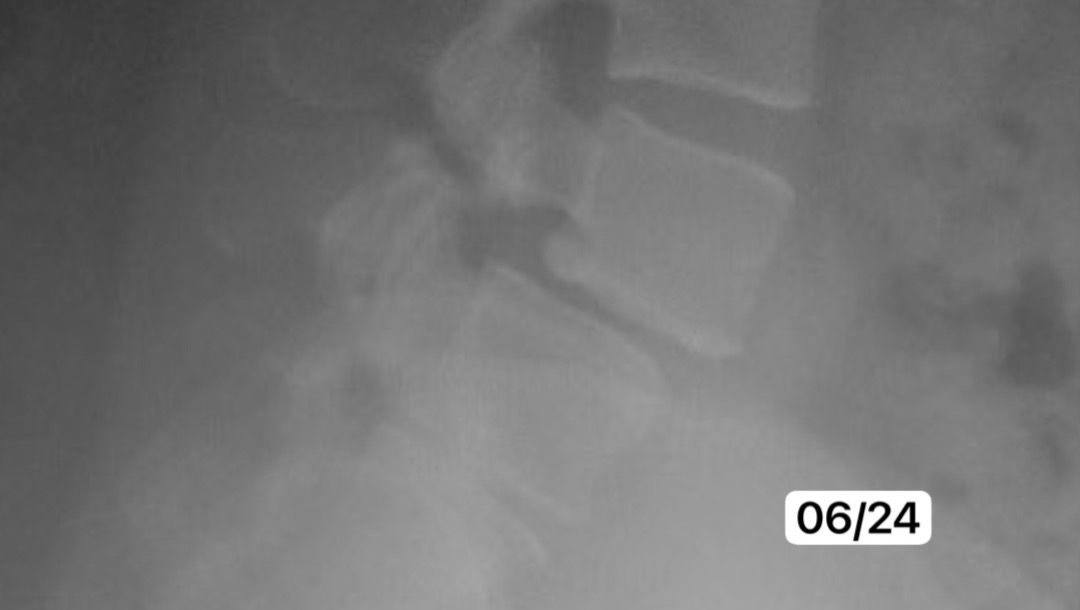

(x-ray taken June 2024)